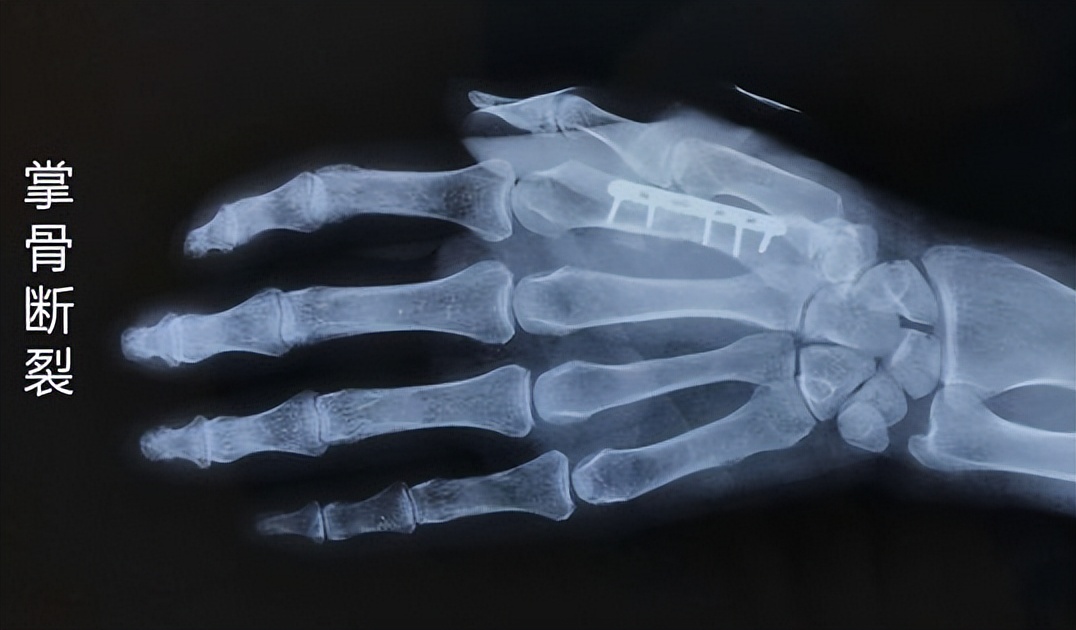

根据医院开具的疾病证明书显示,韦女士患有多处软组织挫裂伤、开放性指骨骨折、指关节囊破裂以及手部指伸肌腱损伤等病情。

这些损伤涉及到手部的多个组织和结构,需要综合治疗和恢复。

本案中巫先生将韦女士打成多处软组织损伤,并伴有指骨开放性骨折。